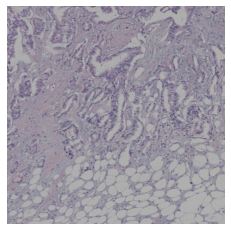

We also analyse the activation maps for each model using GradCAM as described in section S3. This offers more insight into the areas of the image which are contributing most heavily to the models’ representations. In Figure 4(b) we present some representative examples, however, a larger selection which was chosen at random is presented in Figures S10 to S25. The larger selection makes it easier to see the emergent patterns, including that privileged Siamese models tend to mainly identify features which are strongly present in both inputs, while unprivileged Siamese models tend to learn more diffuse features that are not specific to one cell phenotype or image region. TriDeNT ♆ incorporates both sets of features, learning both features specific to the privileged data and more the general features associated with unprivileged Siamese networks.

We can see in Figure 4(b) panel A that for ERG, the privileged Siamese model focuses almost exclusively on any nuclei which could be endothelial cells. As there are very few endothelial cells in the dataset, it could be an effective strategy to identify anything that could potentially be an endothelial cell to minimise the difference between the representations of the H&E model and the IF mask model. In the corresponding unprivileged Siamese image, we see that the model identifies some of these nuclei, albeit less strongly, but also focuses heavily on the other tissue and even the background, while strongly fixating on two spots of debris in the center of the image. This model has less ‘incentive’ to learn the weak features related to endothelial cells as these occur rarely and are not easy to detect, while more generic strong features such as the presence of connective tissue and the prevalence of background are more common and predictable from augmented images. We see that TriDeNT ♆ combines these two feature sets, strongly identifying nuclei while also identifying the connective tissue.

In panel C we see a similar pattern, with the privileged Siamese model fixating solely on the nuclei, while the TriDeNT ♆ model takes a more balanced approach. The unprivileged Siamese model appears to focus on a single cluster of nuclei while neglecting others, and similarly identifies an area of fibroblasts with its distinctive pattern but does not others.

In contrast to panels A and C which represent models with poor privileged Siamese results, panels B and D represent models whose privileged Siamese results were comparable to both TriDeNT ♆ and even the supervised baseline. It is therefore interesting to note that there are far more similarities between the privileged Siamese and TriDeNT ♆ models in both cases. Particularly in panel B, TriDeNT ♆ and the privileged Siamese model return virtually identical heatmaps, with both strongly identifying epithelial nuclei and neglecting the same areas of connective tissue. The unprivileged model in this case appears to focus solely on the centre of the image, giving a significantly different heatmap to the other panels.

Panel D again shows the previous pattern, with the privileged Siamese model identifying the features strongly present in the privileged data – fibroblasts – while neglecting the nuclei present. TriDeNT ♆ also strongly identifies the connective tissue, but, unlike the privileged Siamese model, does not completely neglect the nuclei. The unprivileged Siamese model primarily identifies background, and does not appear to identify the nuclei in this example.